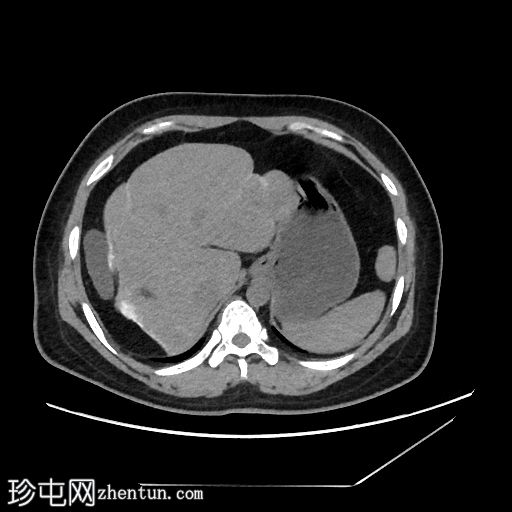

平扫

线状包膜和实质钙化,呈“龟背样”外观

乙状结肠和降结肠壁钙化